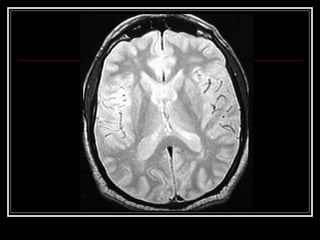

Exames de Imagem Qual a primeira escolha na emergência? Por quê? Qual o método mais sensível?

Exames de ImagemQual a primeira escolha na emergência? Por quê? Qual o método mais sensível?